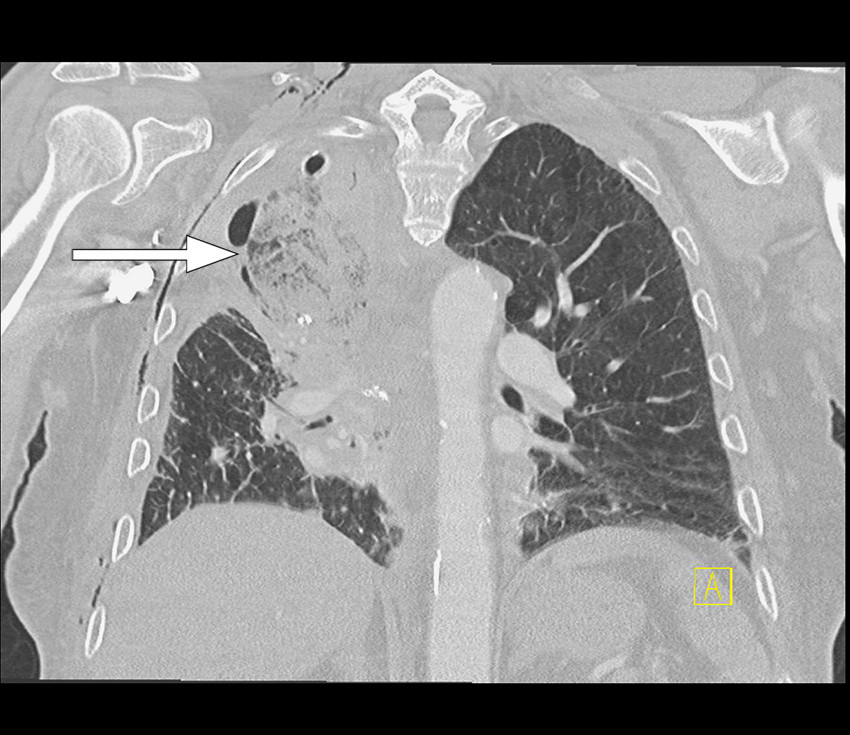

A CXR was performed later the same day for closer monitoring. This did not show any significant change. Hence, the patient was referred for a CT scan for further diagnostic imaging. Contrast-enhanced chest CT performed the evening of the same day demonstrated the middle lobe located apically with extensive ground-glass opacities and patchy consolidation, as well as interlobular septal thickening (Figure 2). The middle lobe appeared to be nearly completely devascularised. The proximal middle lobe bronchus was obliterated and transverse sections revealed subtle swirl sign in the middle lobe, suggesting twisting. The radiological findings raised suspicion of middle lobe torsion.

CXR findings that may raise suspicion of lobar torsion are opacities in an unusually oriented pulmonary lobe which may change position in a short space of time (2, 4). On CT, a tortuous lobe will usually demonstrate reduced contrast enhancement as well as consolidation and/or ground-glass opacities. A tortuous lobe may develop air retention and congestion, leading to lobe expansion and interlobular septal thickening respectively as manifestations of interstitial oedema. There is tapered obliteration of the bronchovascular structures of the lobe near the hilum and the position may be altered, as on X-ray. The development of these changes depends on the degree and duration of torsion. The radiological findings in our patient were consistent with findings previously described in literature.